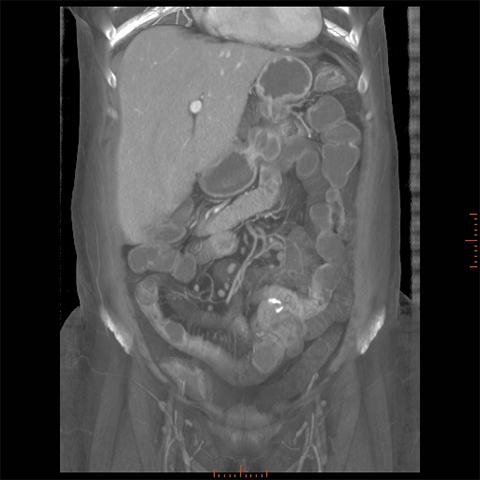

56 year-old male with Crohns Disease presents with persistent abdominal pain and diarrhea. [3 of 4]